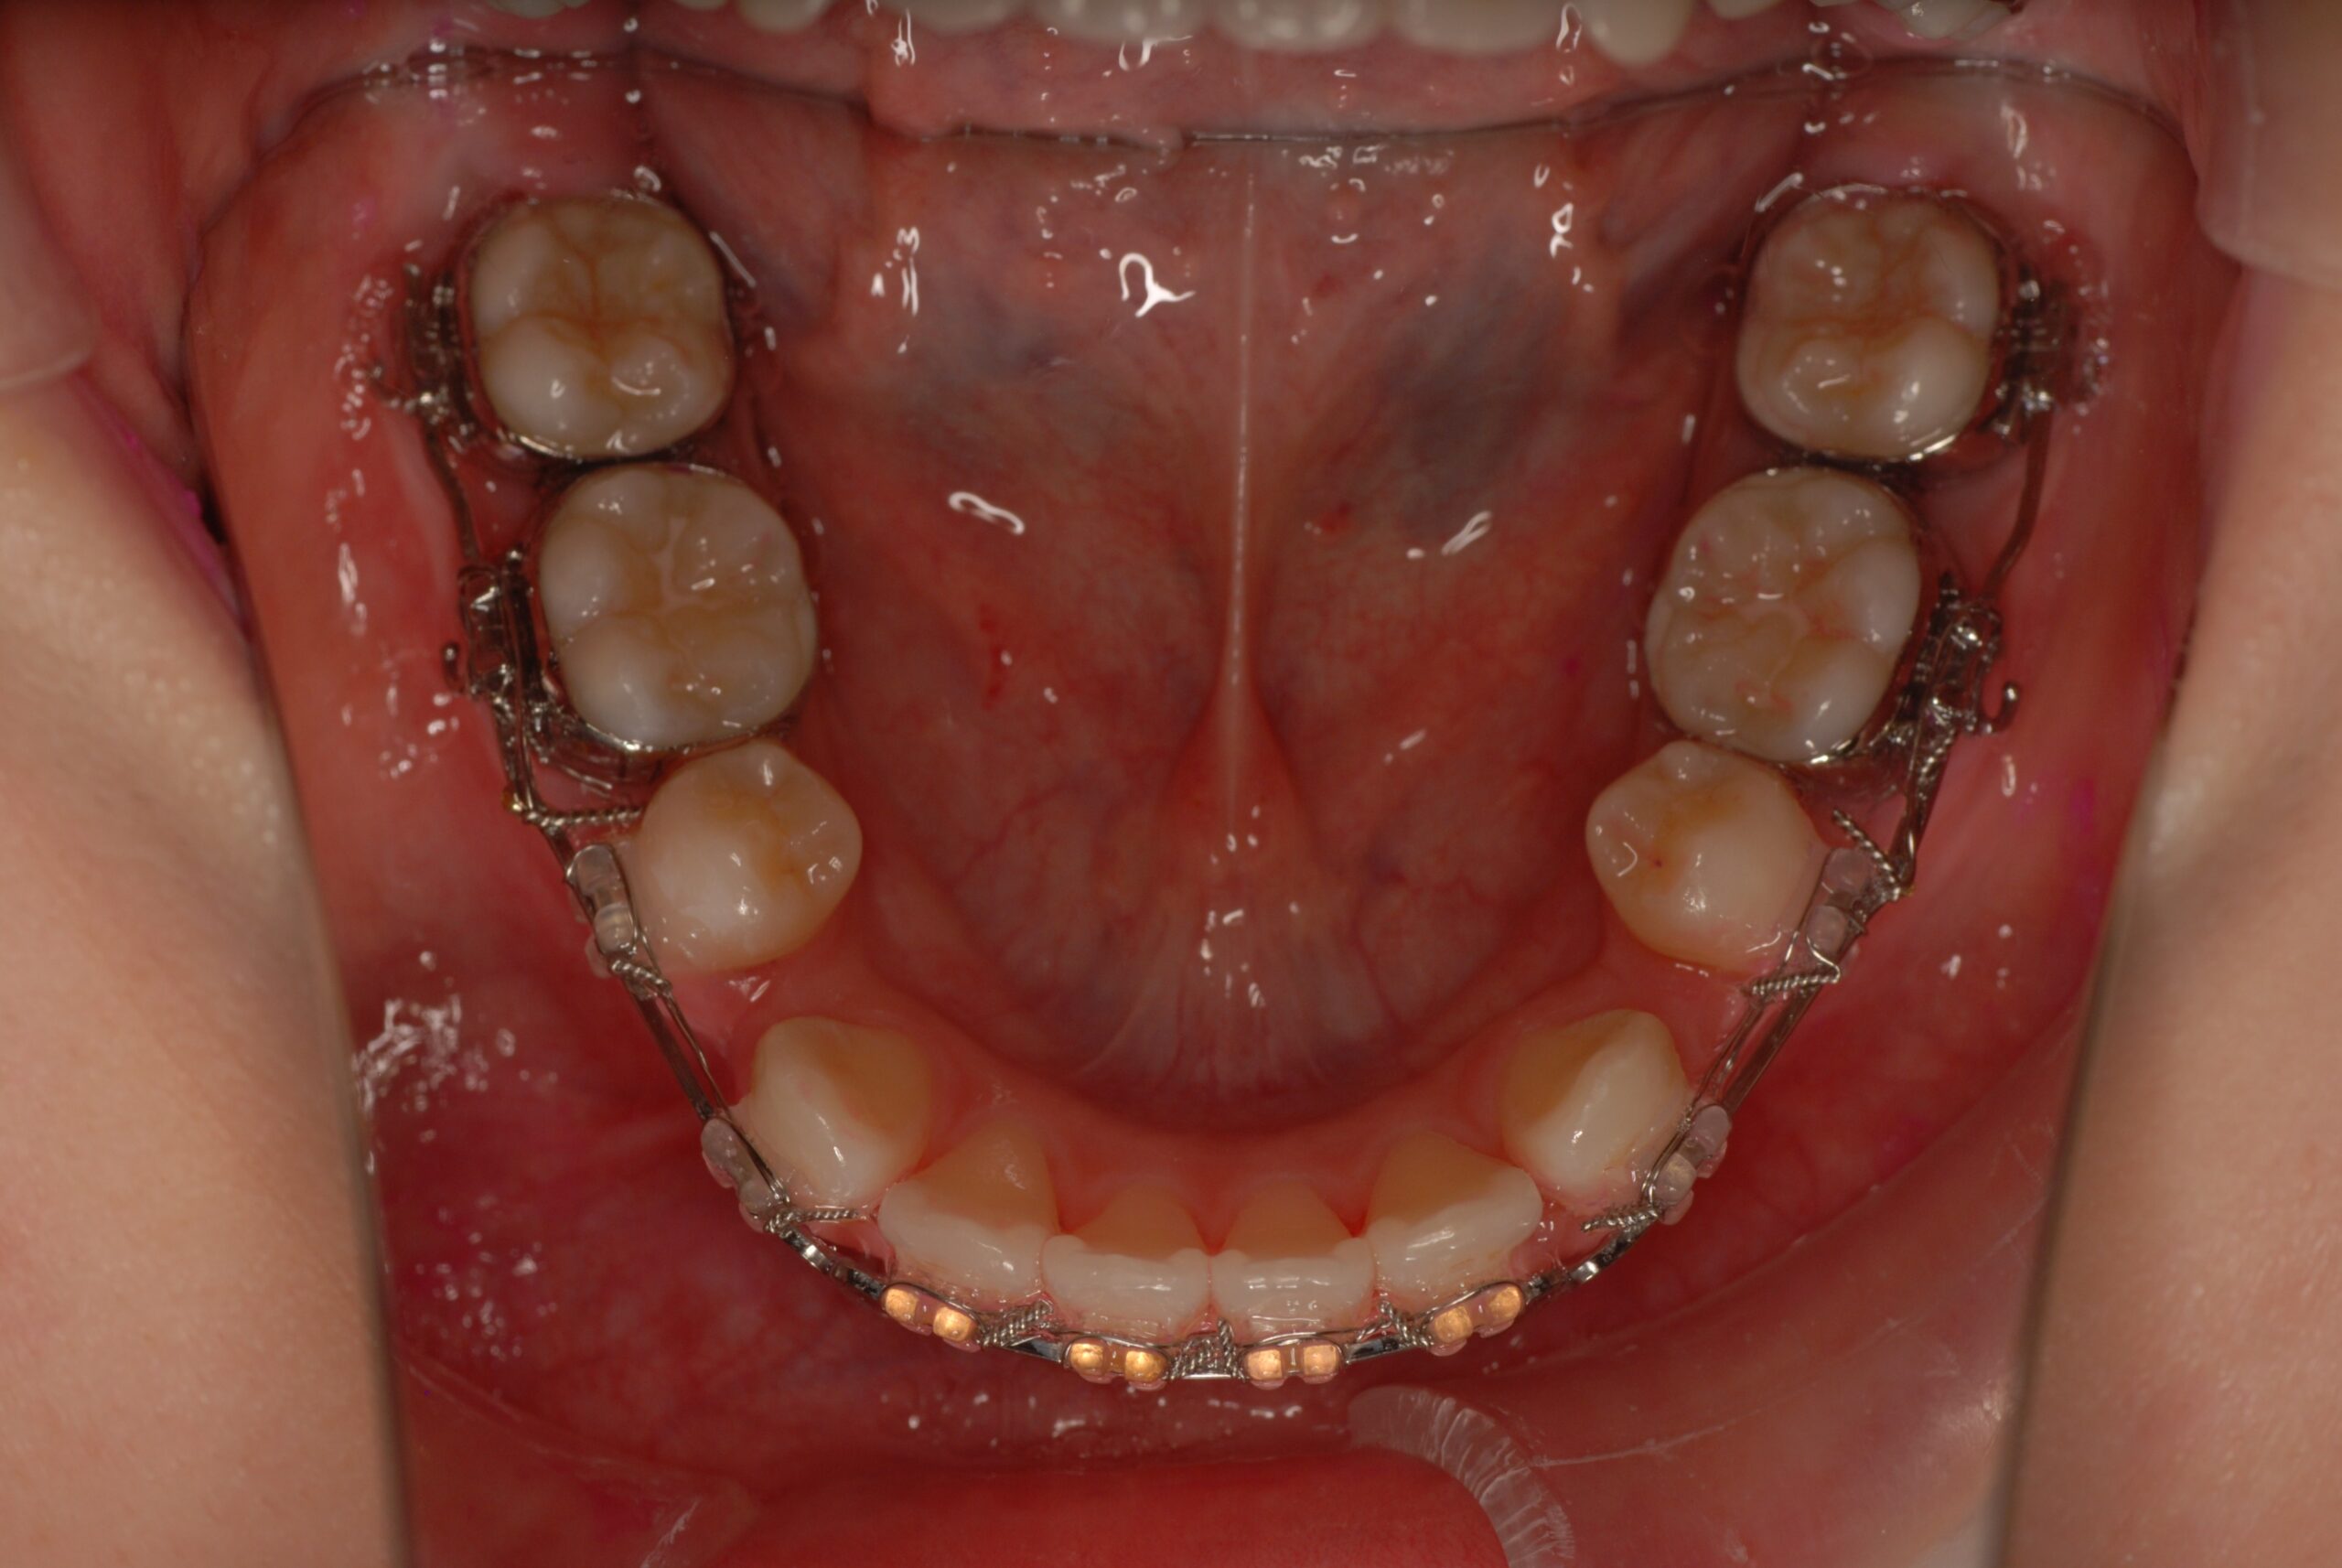

Progress

- 上顎前突、叢生。 上下顎第一小臼歯を抜歯し、抜歯空隙を利用し、顎外固定装置としてヘッドギヤを併用しながら、上顎前歯を可及的に後退させる。